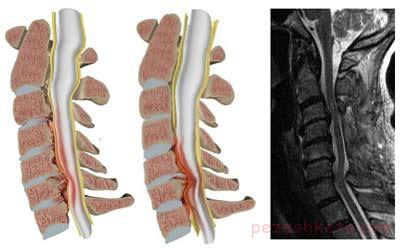

التهاب نخاع گردنی را میلوپاتی می‌گویند. این التهاب می‌تواند به علت تنگی کانال گردن یا اصطلاحاً تنگی نخاع گردنی باشد. تنگی کانال خود می‌تواند مادرزادی بوده یا در اثر آرتروز به ‌وجود آید. آرتروز گردنی شایع‌ترین علت تنگی کانال گردن و فشار به نخاع یا میلوپاتی است. کاهش ارتفاع دیسک، باعث کاهش قوس گردن که به صورت لوردوز است می‌شود. در نتیجه لیگامنتوم فلاوم بر روی خودش چین می‌خورد به‌علاوه استئوفیت مفاصل لوشکا و فاست و همچنین اسئوفیت لبه‌های مهره‌ها باعث تنگی کانال نخاع می‌گردد. فشار به نخاع حاصله از تنگی کانال گردنی به آرامی پیشرفت می‌کند.

میلوپاتی در مواردی زیادی عکس‌های رادیولوژی فشار زیادی به نخاع را نشان می‌دهد ولی بیمار علامت جدی ندارد. به‌نظر می‌رسد نخاع تا حدی در برابر تغییر شکل کانال نخاعی مقاوم است. در صورتی که بیمار سرش را به عقب ببرد ممکن است نخاع تحت فشار بیشتری قرار گیرد. با خم کردن گردن به جلو ممکن است سطح کانال نخاعی بازتر شود. اما احتمال فشار به نخاع توسط استئوفیت‌هایی که از لبه دیسک بیرون زده است وجود دارد.

در بررسی رادیولوژی ساده باید به اسئوفیت‌ها توجه شود. از لحاظ ناپایداری عکس‌های لترال گردن در حالت فلکشن و اکستنشن باید گرفته شود.لوردوز طبیعی گردن بین 13 ± 21 درجه است. با افزایش سن قوس گردن کم می‌شود و در حدود ده درصد افراد بدون علامت گردنی به صورت کیفوز است. اندازه کانال گردنی طبیعی در بالغین 18-17 میلیمتر است(بین 20-13 میلیمتر). در صورتی که قطر کانال به 13-10میلیمتر برسد فشار به نخاع اتفاق می‌افتد. در این حالت تنگی نسبی کانال نخاع گردنی اطلاق می‌شود. در صورتی که قطر کانال به زیر 10 میلیمتر برسد انسداد مطلق کانال نامیده می‌شود. در این حالت در صورت حرکت سر به عقب قطر کانال بسیار کمتر شده و به نخاع فشار وارد می‌شود. این حالت در ترمز ناگهانی اتوموبیل و یا زمین خوردن ممکن است ایجاد شده و باعث آسیب جدی به نخاع گردد.

دقیق‌ترین روش اندازه‌گیری کانال نخاعی توسط سی‌تی‌اسکن است اما ام. ‌آر. ای. بهترین روش دیدن تغییرات در خود نخاع است.وجود سیگنال غیرطبیعی در نخاع لزوماً ارتباطی با نتایج بالینی ندارد. اگر ضایعه دیده شده در ام. آر. ای. در 2T حاشیه واضحی داشته باشد نتایج بدتری نسبت به گردنی که حاشیه ضایعه واضح نیست دارد. در مطالعه‌ای در 20 درصد بیمارانی که درمان غیرجراحی شده بودن افزایش سیگنال نخاع بعد از 3 سال از بین رفته بود.